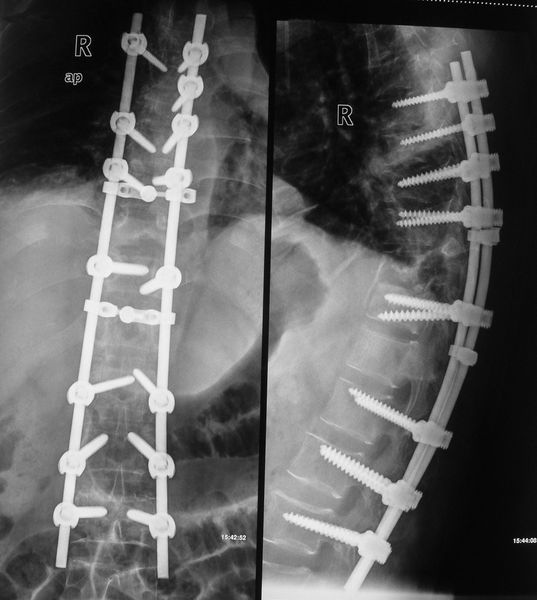

VCR截骨术治疗陈旧性脊柱结核严重后凸畸形

537x600 - 41KB - JPEG